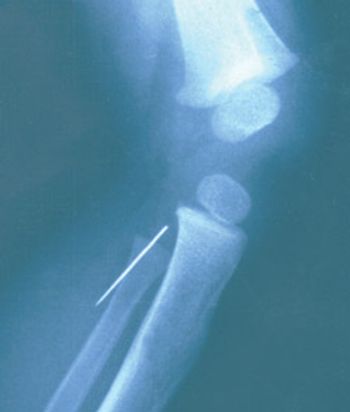

A thriving boy was brought to the office 3 weeks after his first birthday. His mother reported that there was something wrong with his knee. On visual examination, the knee appeared perfectly normal. On palpation, however, a 4-cm linear induration was evident over the knee fat pad, just medial and distal to the patella. It appeared soft, crepitant, and associated with the skin. No tenderness was noted on palpation; the infant did not object to palpation of this density any more than to auscultation, otoscopy, or anthropometric measurements.